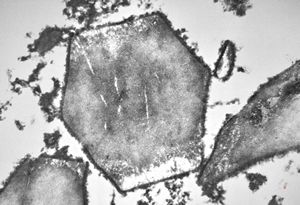

M,62y. | crystalline inclusion in endoplasmic reticulum - bone marrow, plasmocytoma